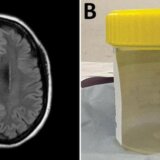

Neurohirurškinja Hari Prija Bandi istražujući misteriozne simptome jedne žene u jednoj australijskoj bolnici, kaže da je u mozgu žene našla crva od osam santimetara.

Bandi je obavila biopsiju kroz rupu na lobanji pacijenta u bolnici u Kanberi prošle godine i kleštima izvukla parazita.

Stvorenje je bilo larva australijskog autohtonog okruglog crva za koji se ranije nije znalo da može biti ljudski parazit.

Bandi i lekar za infektivne bolesti iz Kanbere Sanjala Senanaiake su autori članka o izuzetnom medicinskom slučaju objavljenom u najnovijem izdanju časopisa koji se bavi medicinskim dostignućima.

Žena je primljena u bolnicu nakon što je tokom tri meseca doživela zaboravnost i pogoršanu depresiju. Skeniranje glave je pokazalo promene u njenom mozgu.

Senanaiake je očekivao da će biopsija mozga otkriti rak ili apsces.